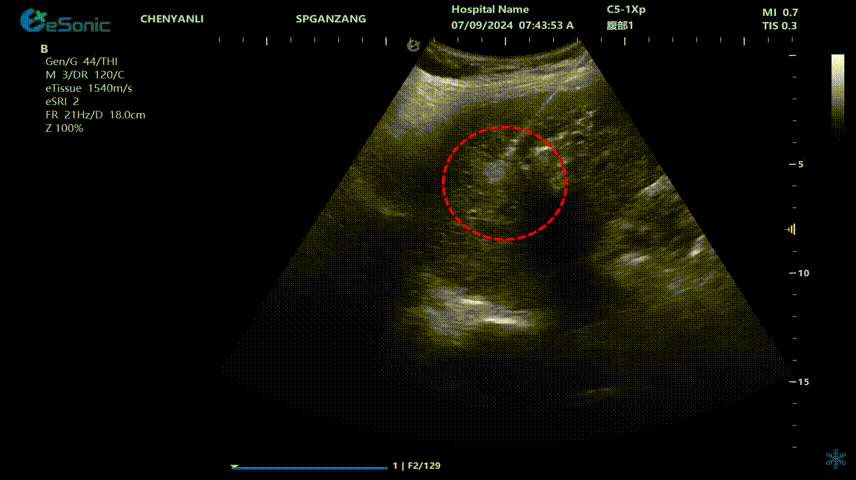

治疗过程:超声介入科董刚教授决定采用射频消融技术进行治疗,在超声引导下,将射频消融针经皮穿刺插入肝脏肿瘤组织内,根据肿瘤的大小和形状,调节好射频功率和时间,使肿瘤病灶组织在高温下被精准灭活。手术过程中,密切监测患者的生命体征和肝功能变化。

640 (2).gif

肝癌射频消融动态视频

红圈为病灶位置

肝癌射频消融:全麻下彩超探头引导射频针分别植入肝右叶两个稍高回声结节,固定消融,至结节全部为强回声覆盖,覆盖良好,缓缓灼烧针道后退针。